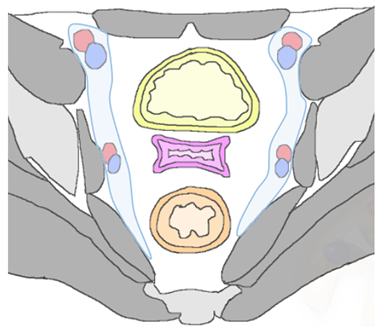

| Type of Recurrence | Imaging Findings |

|---|---|

| Regional | |

| Lateral Pelvic sidewall ![]() | Pelvic sidewall recurrence is defined as a tumor extending within 3 mm and abutting the obturator internus or piriformis muscles with concomitant loss of fat planes. Other findings include:

|

| Lymphadenopathies | |

| Paracervical, parametrial, internal and external iliac, obturator, sacral, common iliac and para-aortic lymph nodes. |